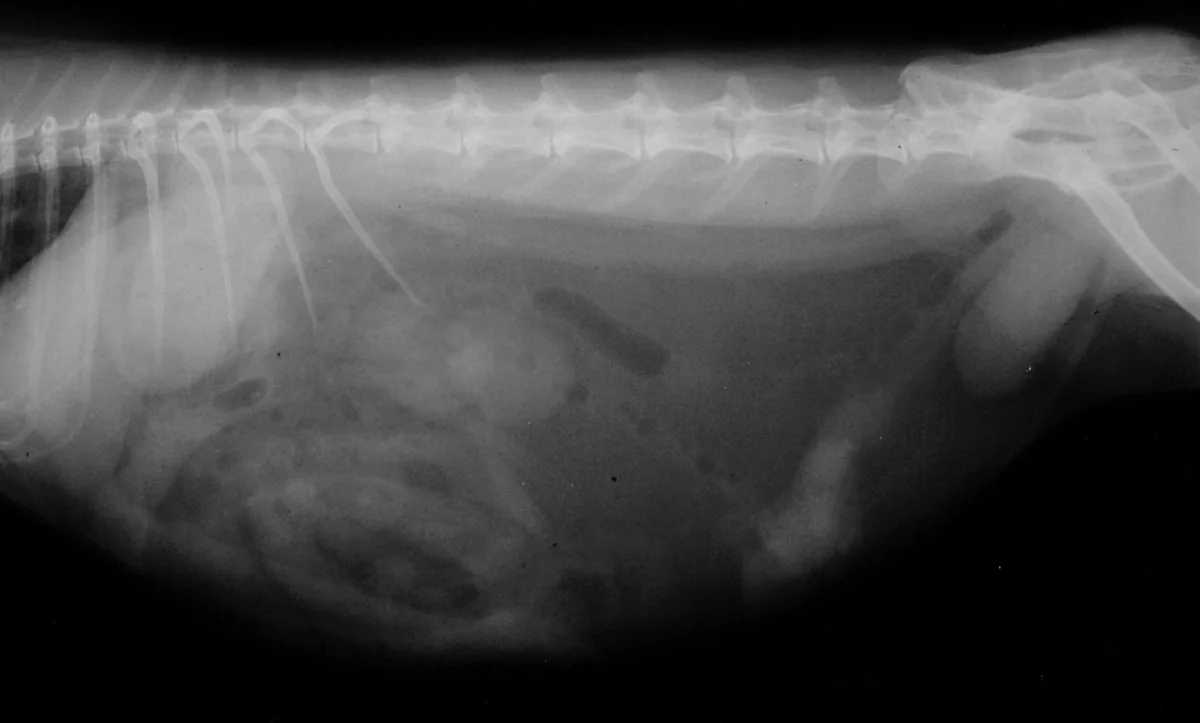

A soft-tissue opacity is apparent on the lateral radiograph (Figure 2) between the bladder and colon. Laparotomy was performed. What was removed is shown in Figure 3. Histopathology results revealed uterine adenocarcinoma. Uterine adenocarcinoma is a slow-growing tumor. Removed early in disease, the cancer is curable by ovariohysterectomy; no ancillary treatment is required. In this case the uterus was removed and there were no signs of metastasis. The rabbit was doing well when presented a year later for a checkup. Uterine adenocarcinoma is common in unspayed female rabbits. The only sign may be blood in the urine. In this case, the red urine did not alert the owners because the patient has had a history of porphyrin-colored urine and the red coloring from blood looked no different from porphyrin pigments.